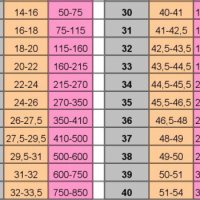

Починаючи з цього терміну, 32 тиждень вагітності, вага вагітної жінки може бути більше вже на 11 кг. Іноді, цей показник змінюється в більшу або меншу сторону, все залежить від організму мами і розмірів дитини. Висота розташування дна матки на 32 тижні дорівнює 32-33 см. А розмір живота у кожної майбутньої мами різний, він залежить від індивідуальних особливостей жінки. Якщо у вас 32 тиждень вагітності, фото животиків можете подивитися в Інтернет і порівняти зі своїм.